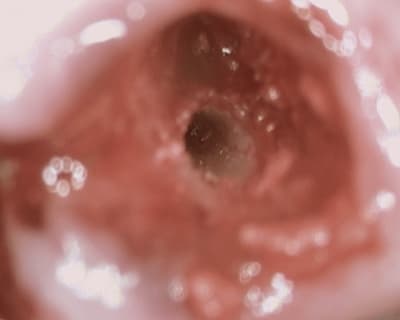

des photos d'un cas d'aujourd'hui avec le shuttle retiré ( 8 premières photos)

les 4 dernières c'est avec le foret , la dernière photo c'est un cas d'extraction implantation d'aujourd'hui aussi on voit la nouvelle alvéole après le forage ( désolé pour la qualité de photo...)